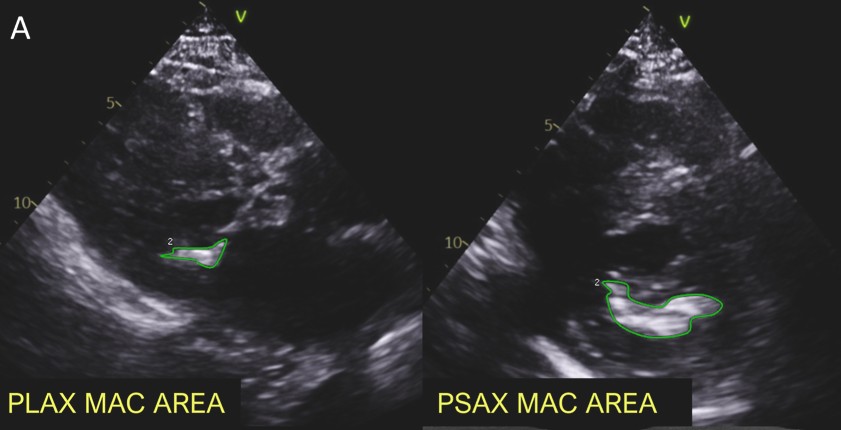

Para tanto, os participantes tiveram a área da calcificação do anel mitral medida tanto no eixo curto quanto no eixo longo da janela paraesternal em frame único com a melhor visualização do anel mitral.

Se a calcificação estivesse presente em segmentos descontínuos, esses eram medidos separadamente. Além da quantificação da área, foi também realizado a porcentagem do total da calcificação em relação a circunferência do anel valvar.